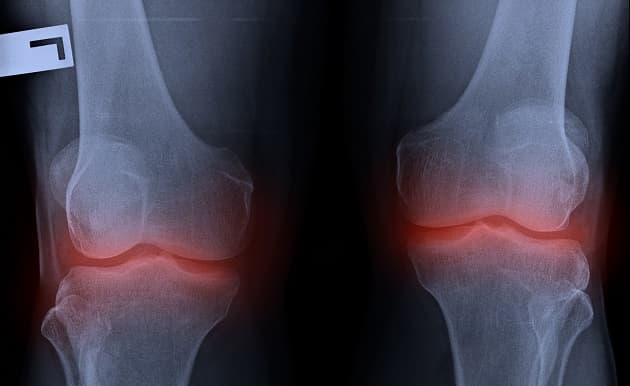

Intra-articular injection of adipose tissue for knee osteoarthritis

Treatment of osteoarthritis with autologous and microfragmented adipose tissue